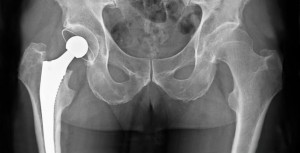

Infección de prótesis articular: qué hacer cuando no se puede operar

El tratamiento antibiótico supresor prolongado podría ser eficaz en pacientes ancianos en los que la opción quirúrgica no es una alternativa. European Journal of Clinical Microbiology & Infectious Diseases, abril de 2017